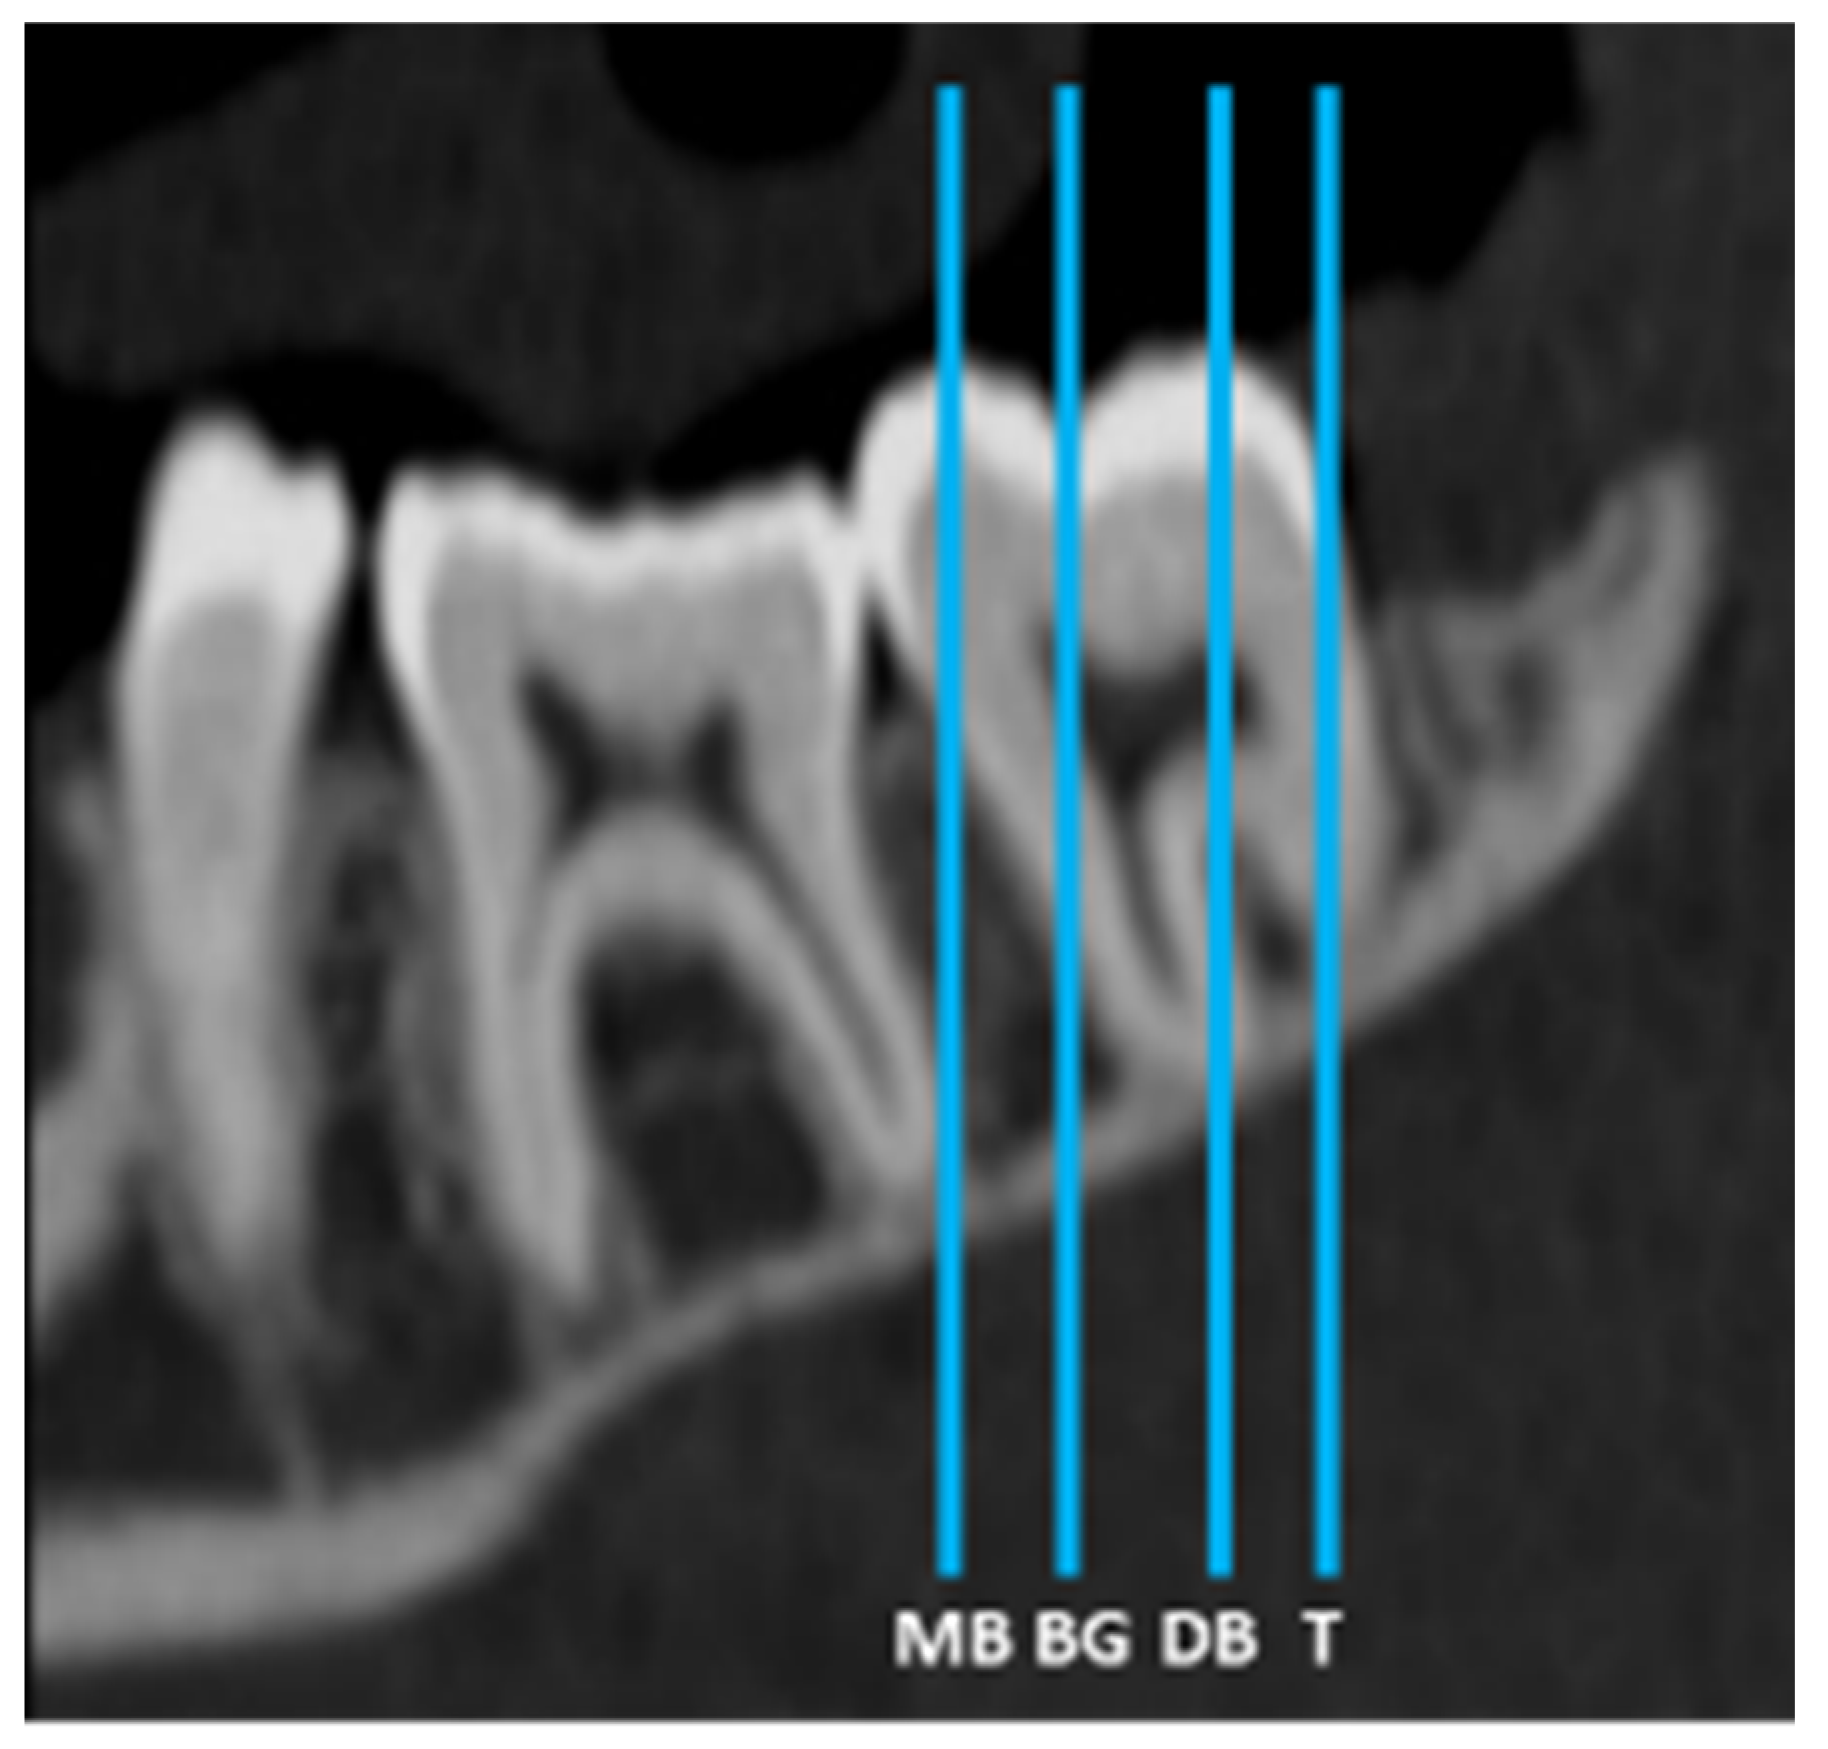

2. Materials and Methods